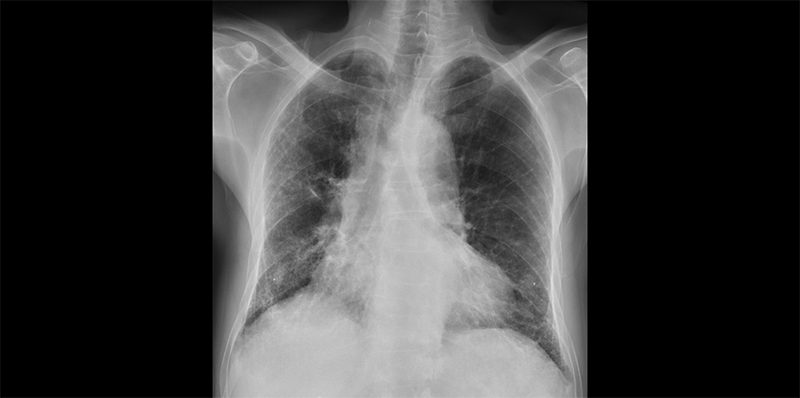

X-thorax: Bibasale en subpleurale reticulaire afwijkingen

Een 62-jarige man bezoekt zijn huisarts omdat hij tijdens het sporten heeft gemerkt dat zijn conditie het afgelopen jaar achteruit is gegaan. Het tempo wordt lager. Hij heeft verder geen klachten, maar zoekt een verklaring. Hij heeft ongeveer 20 pakjaren gerookt, maar is enkele jaren geleden gestopt. Zijn huisarts hoort aan beide zijden crepitaties over de basale longvelden (beluister het geluidsfragment). Verder ziet ze trommelstokvingers (ook wel clubbing genoemd). Vanwege basale crepitaties en kortademigheid denkt ze aan hartfalen. Een normaal NT-proBNP en ecg maken dit echter minder waarschijnlijk. De huisarts besluit een thoraxfoto te maken. Hierop zijn in de basale longvelden aan beide zijden reticulaire afwijkingen te zien (zie foto hierboven). Een aanvullende spirometrie laat normale volumina zien en geen obstructie. De huisarts verwijst de patiënt voor nader onderzoek naar een longarts. Deze vindt bij uitgebreidere spirometrie wel een laag normale diffusie (DLCOc) van 85% voorspeld. Op de high resolution computed tomografiescan zijn tekenen van longfibrose te zien. De longarts vindt geen onderliggende oorzaak van longfibrose. Tijdens een multidisciplinair overleg wordt de diagnose idiopathische pulmonaire fibrose gesteld. Na een korte observatieperiode met een duidelijke achteruitgang van de longfunctie, start de patiënt met de fibroseremmer nintedanib.

Aanvullend longfunctieonderzoek laat meestal een volume-restrictie zien, zonder obstructie. Als bij spirometrie een verlaagde FVC wordt gemeten, moet eerst worden nagegaan of dit komt door een technisch onvoldoende spirometrie. Zo niet, dan is een vastgestelde volumerestrictie altijd reden voor verder onderzoek, wat meestal verwijzing naar de longarts betekent. Zoals de casus illustreert kunnen de longvolumina, zoals vitale capaciteit, in de beginfase nog normaal zijn, terwijl de patiënt al klachten heeft. Een patiënt ouder dan 45 jaar met progressieve dyspneuklachten en/of droge hoest, vermoeidheid en/of crepitaties en/of trommelstokvingers, moet bij twijfel aan de diagnose een verwijzing naar de longarts krijgen. Een normale spirometrie, maar onbegrepen klachten van inspanningsdyspneu (een discrepantie tussen de ernst van de klachten en objectieve bevindingen), een snel progressief beloop of klachten die ondanks een optimale behandeling aanhouden, kunnen ook een reden zijn om vroegtijdig naar een longarts te verwijzen. Deze doet dan een uitgebreider longfunctieonderzoek met een totale longcapaciteit en een diffusiemeting. Bij de diagnostiek van longfibrose staat de high resolution computed tomografie (HRCT) (aangevraagd door de longarts) centraal. Een normale thoraxfoto sluit longfibrose namelijk niet uit.5 In een vergevorderd stadium kan op een X-thorax al reticulatie of een verhoogde densiteit van het longparenchym zichtbaar zijn, zoals ook in de casus het geval is. Ook kan de huisarts de thoraxfoto gebruiken om andere oorzaken van inspanningsdyspneu uit te sluiten.